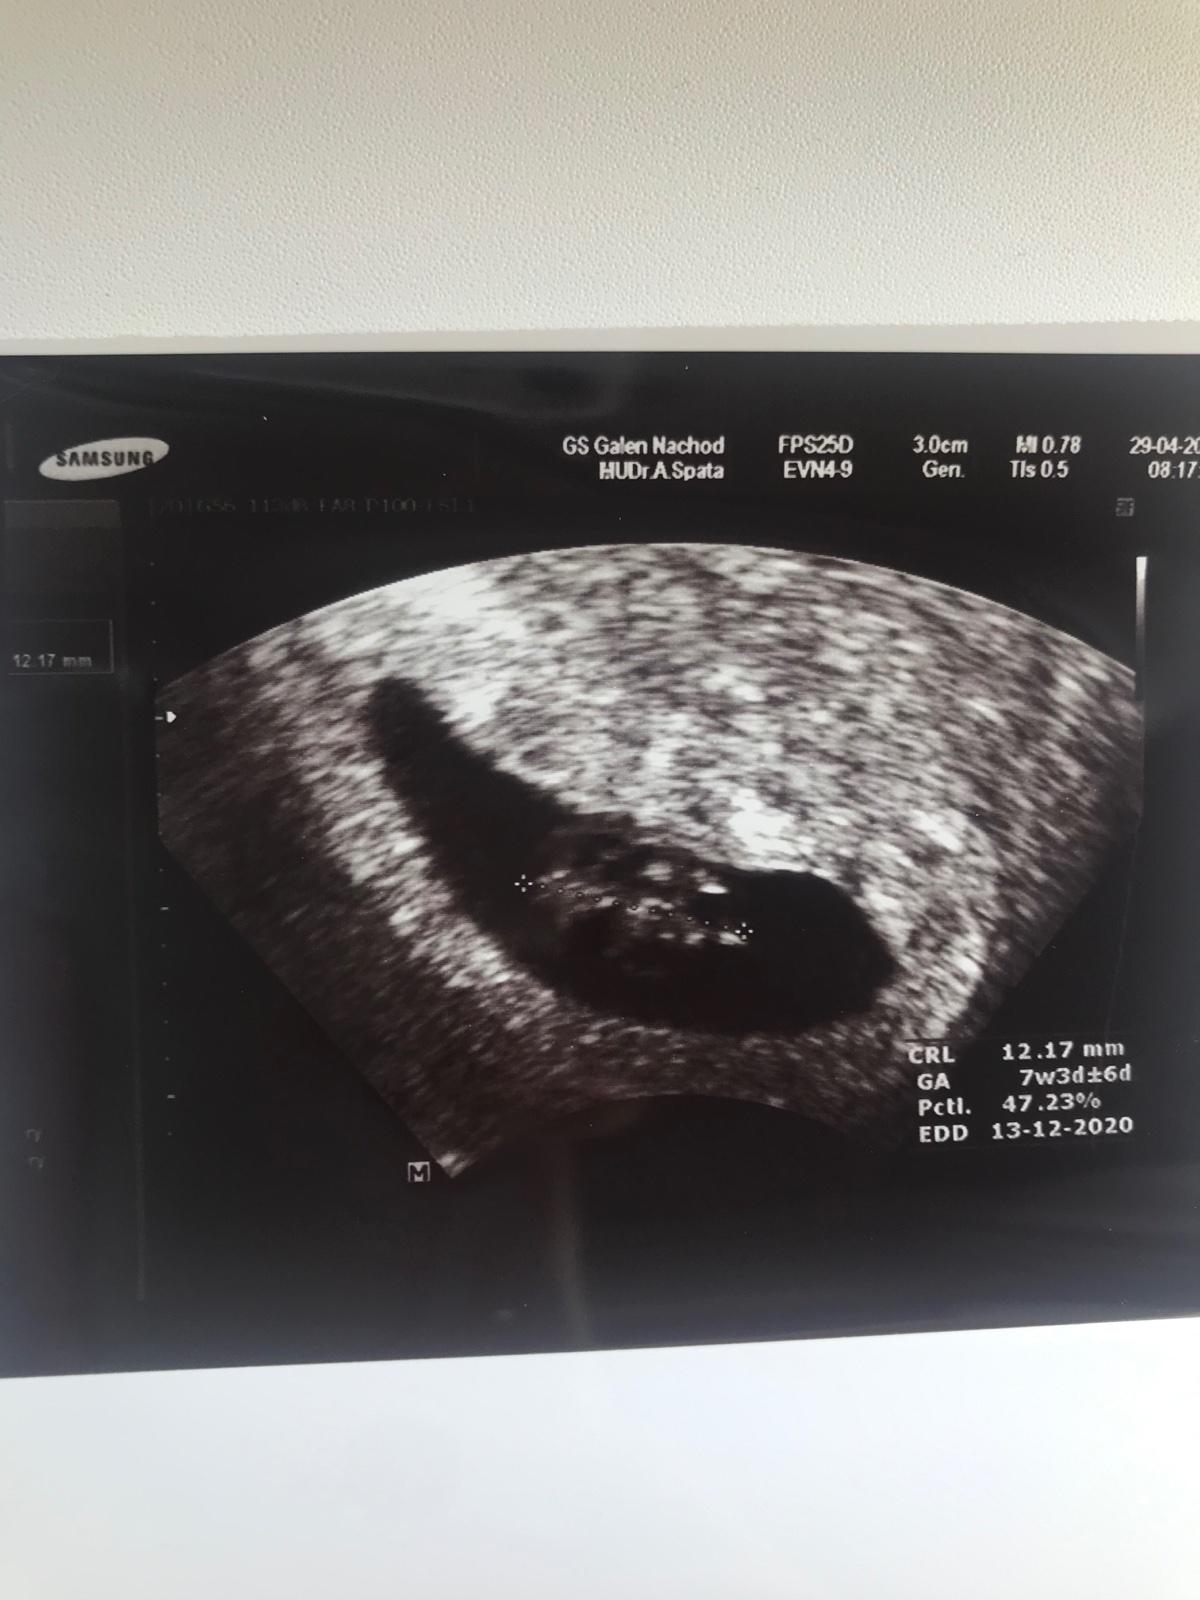

Co kde miminko na fotce z ultrazvuku má. Poznáte to některá?

@andyskarsgard já jsem byla asi v 7 týdnu. Takže tady na té fotce to vypadá jako flek. Ale v reálu bylo miminko hezčí. Ale aspoň, že jsem slyšela srdíčko. 😊

@rnika Jo bylo to pěkné. Aspoň jsem si mohla trošku oddychnout. 😊no nahoře byla hlavička. Takže to by asi tak sedělo. Ale z toho šoku fakt už nevím ani jak miminko vypadalo 😀ve středu jdu znovu, tak snad tentokrát už bude větší fešák.

Takhle brzy fakt nic moc nepoznáš... je tam akorát změřená délka plodu... od křížku ke křížku, to je dole i apsané... kolik má mm, jinak by tam mohlo být vidět srdíčko, ale který z těch tmavších flíčk to je nepoznám, určitě bylo při ultrazvuku vidět jak tam tepe. ( na té první větší kontrole už to bude vidět pěkně )